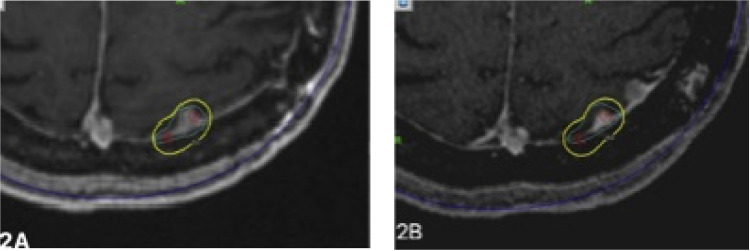

There were a total of 3 meningiomas that had progression of disease whose failure was local (Fig. 1), defined as within the prescription isodose line (Table 3). There were an additional 4 meningiomas that developed marginal failures (Fig. 2), defined as outside the prescription isodose line but within 5 mm. No failures were seen in patients in whom the treatment targeted the surgical cavity and residual disease (n = 5 sf-gamma knife radiosurgery [GKRS], n = 7 hf-GKRS) or who received hf-GKRS. Prescription dose (P = .23) did not correlate with failure.

Figure 2.

Representative magnetic resonance imaging (MRI) images demonstrating the pattern of marginal failure after stereotactic radiosurgery (SRS). (A) Axial view of MRI showing 50% isodose line around the lesion in the parietal convexity and (B) posttreatment follow-up MRI images demonstrating marginal failure within 5 mm of isodose.